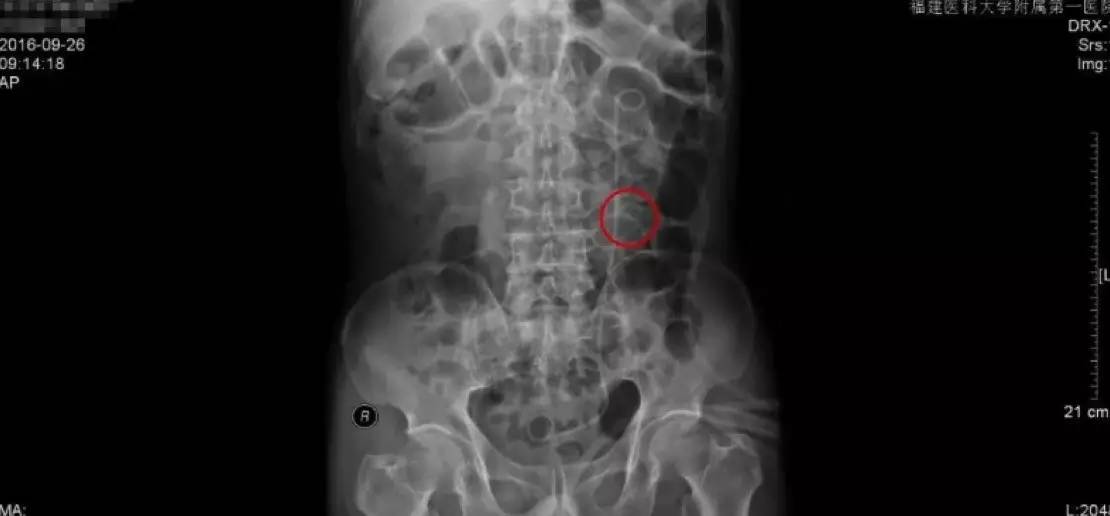

手术后KUB检查报告

手术后的复查主要是通过拍KUB,通过与手术前KUB报告的直观对比,从图中可以看到,原来结石的地方,强化的结石已经消失了,左侧可以看到箭头指示的是一根手术后留置的双J管,这根管的目的是为了防止手术后输尿管狭窄黏连。

由于我们的手术是通过输尿管操作的,对输尿管粘膜不同程度有损伤,如果不留置双J管的话,术后容易造成输尿管黏连狭窄,输尿管最细的地方只有0.5cm,所以狭窄是手术后需要注意的并发症。